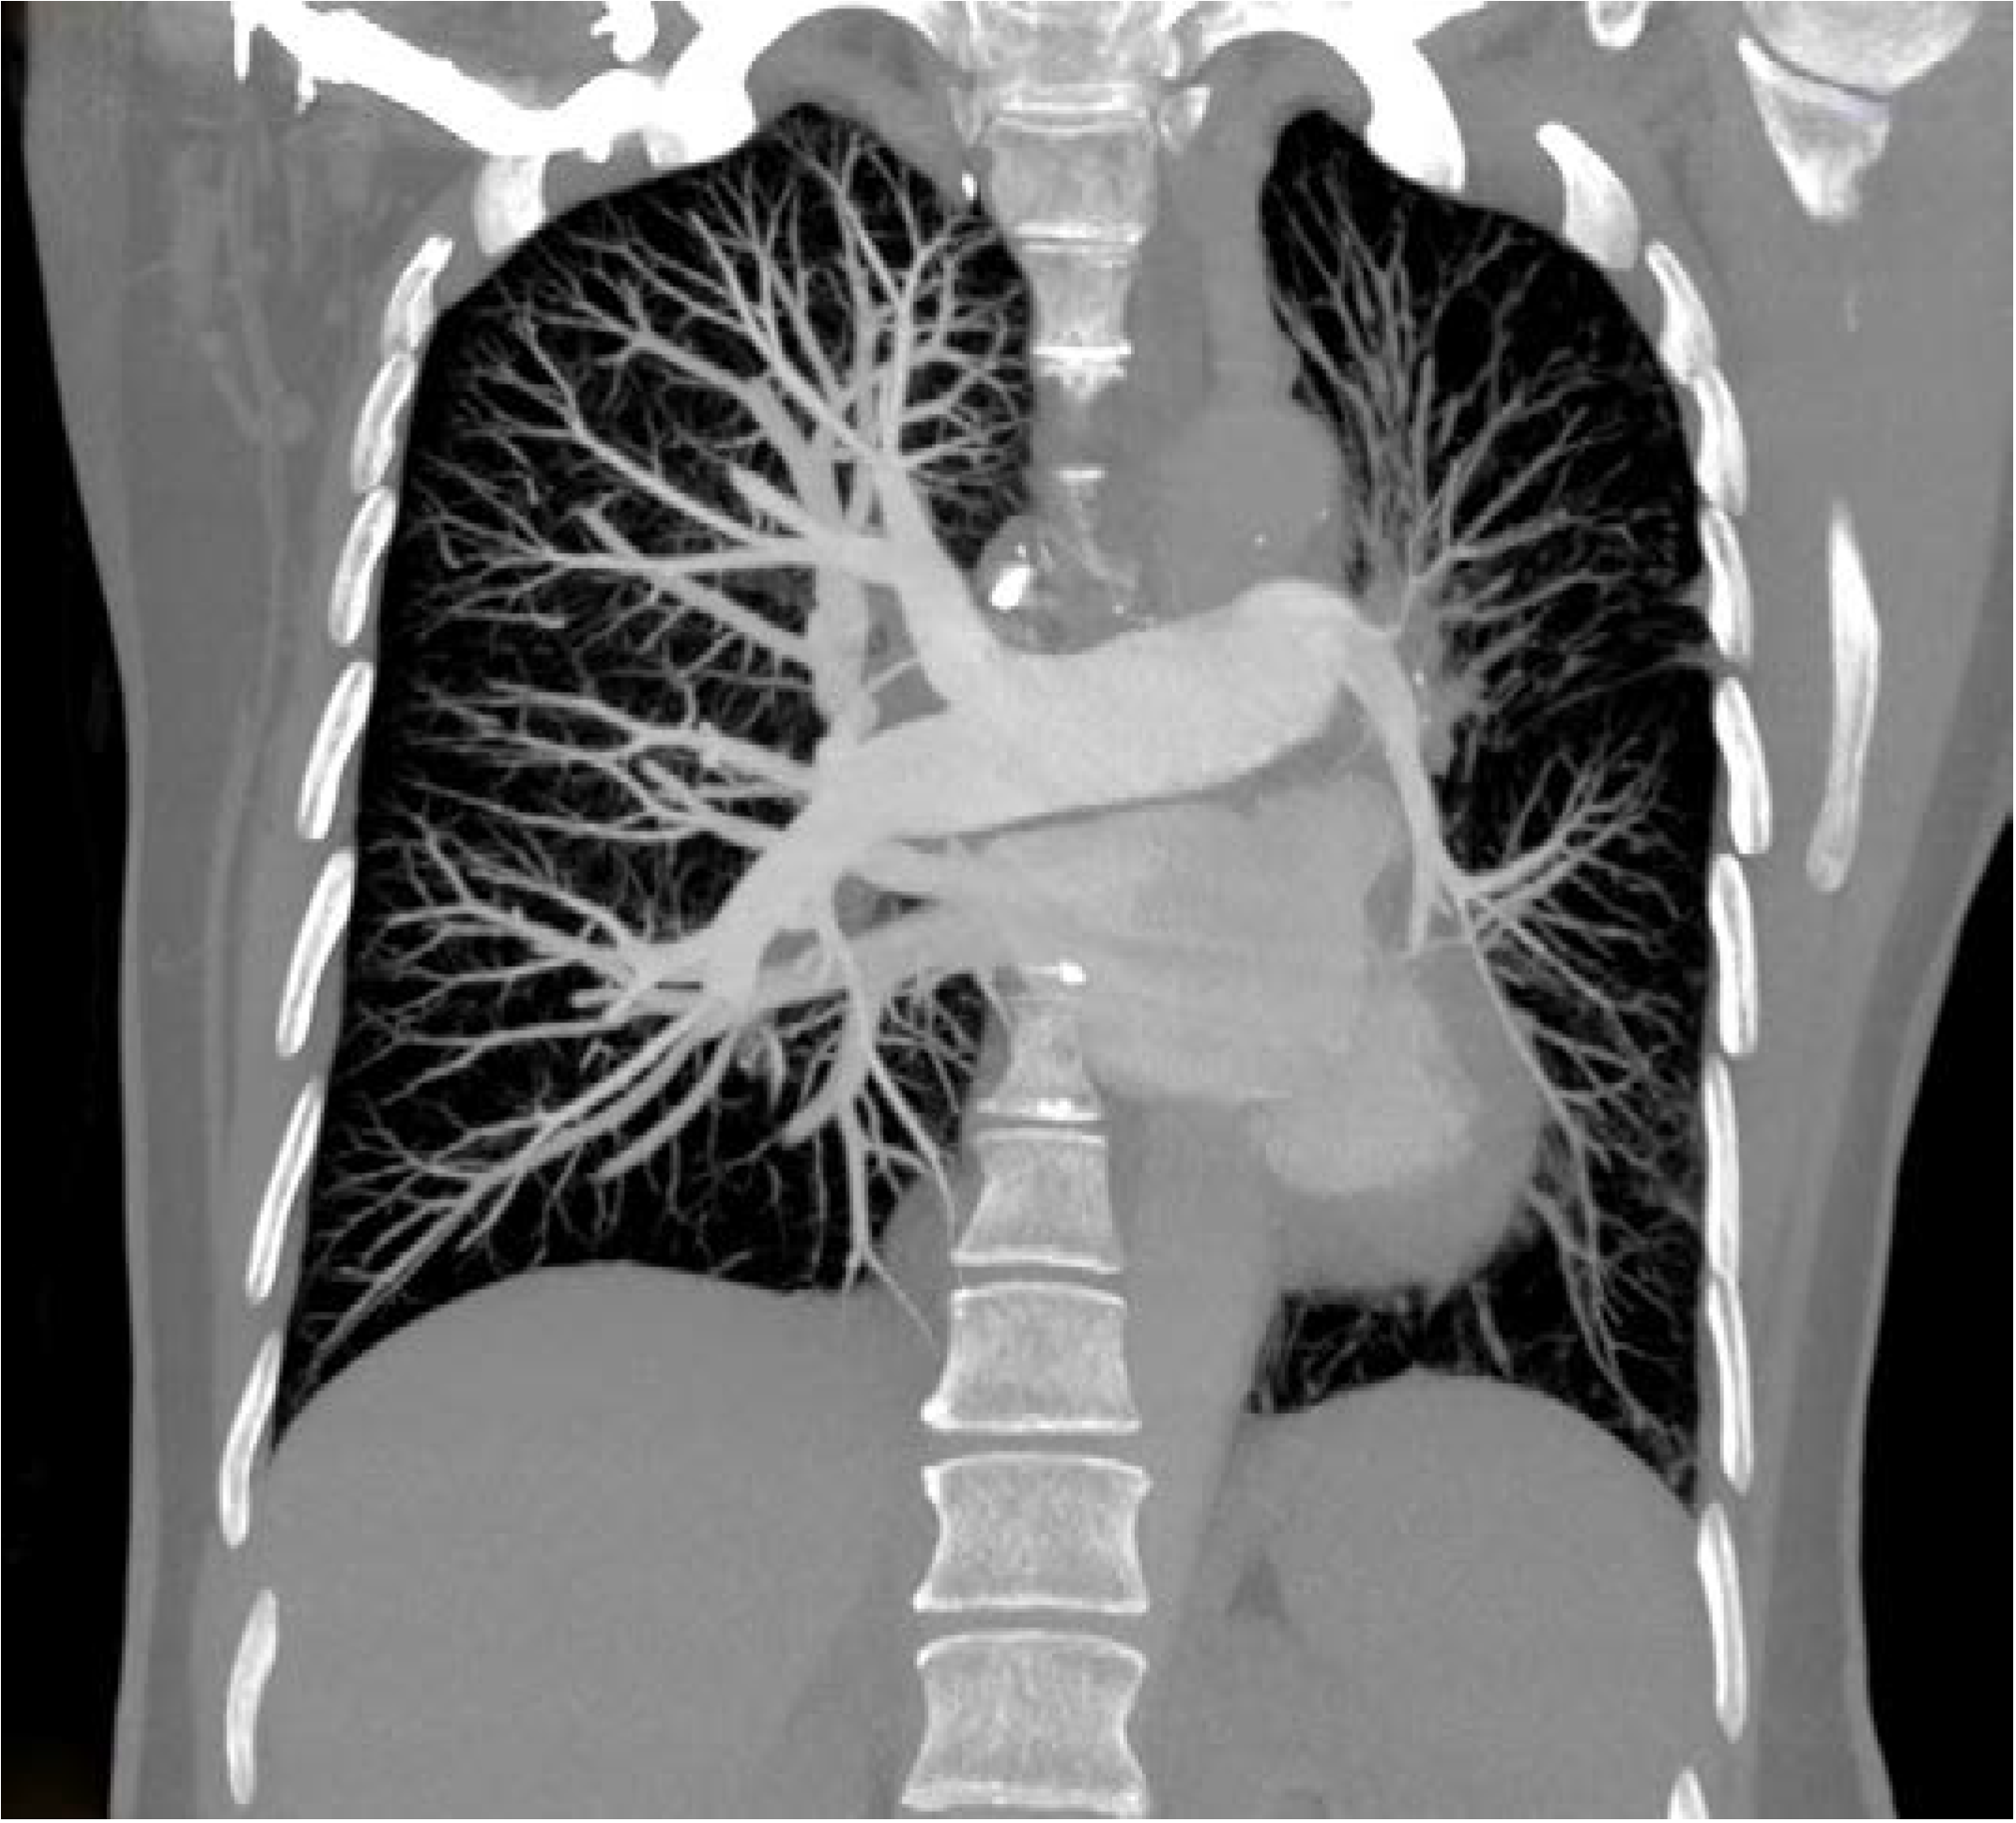

Thorax computed tomography (CT) revealed asymmetry with significantly smaller left lung. The left pulmonary artery immediately after separation was of extremely narrower lumen and so were lobar and segmental branches (Figure 2). Collaterals stemmed from mammary artery and bronchial artery (Figure 3). The results pointed towards UAPA. Subpleurally on the left, apically and basolaterally, scarred changes were noticed.

Thorax CT reveals abnormal pulmonary artery that can be completely absent or finished 1 cm from its beginning or continuing in very narrow lumen, there can be preserved peripheral branches of the pulmonary artery, variable collateral circulation, possibly associated congenital anomalies, parenchymal changes such as mosaic attenuation and bronchiectasis due to recurrent infections [6,10].

Figure 2. Computed tomography (CT) showing rudimentary left pulmonary artery.